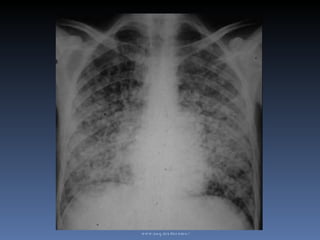

Neumopatía aguda excavada en un paciente VIH positivo, con criptococosis diseminada.  Nódulo pulmonar solitario en un enfermo VIH positivo, con criptococosis diseminanda  www.uaq.mx/rneumo/

Neumopatía aguda excavadaen un paciente VIH positivo, con criptococosis diseminada. Nódulo pulmonar solitario en un enfermo VIH positivo, con criptococosis diseminanda www.uaq.mx/rneumo/